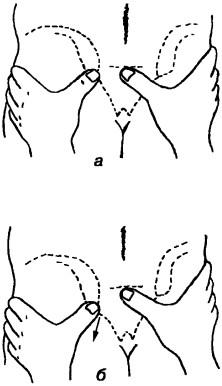

A funkcionális kismedencei vizsgálat tartalmaznia kell az úgynevezett motoros teszt „forog” (gerinc): A páciens áll felálló, háttal az orvos, aki hozza egyrészt egyik hüvelykujját a hátsó felső csípőnyerge, másrészt - a hüvelykujj fel a középső keresztcsonti taréj on a magassága megegyezik a hátsó gerinc. Az orvos kínál a páciens műszakban lábáról a, ugyanabban az időben, ha a testtömeg átvisszük a szemközti oldalán rögzített hátsó gerinc, ünnepelte műszak utólag és oldalirányban (ábra. 142). Ha újra elfog a középső keresztcsonti taréj és a hátsó csípőnyerge oldalán a támasztó láb, a

Ábra. 142. A tanulmány a mobilitás, a sacroiliacális ízület lépve a lábaira, és - megállapítja a hüvelykujját a hátsó gerinc és a középső keresztcsonti taréj (a kiindulási helyzet), - egy elmozdulás a hátsó gerinc lefelé és oldalirányban